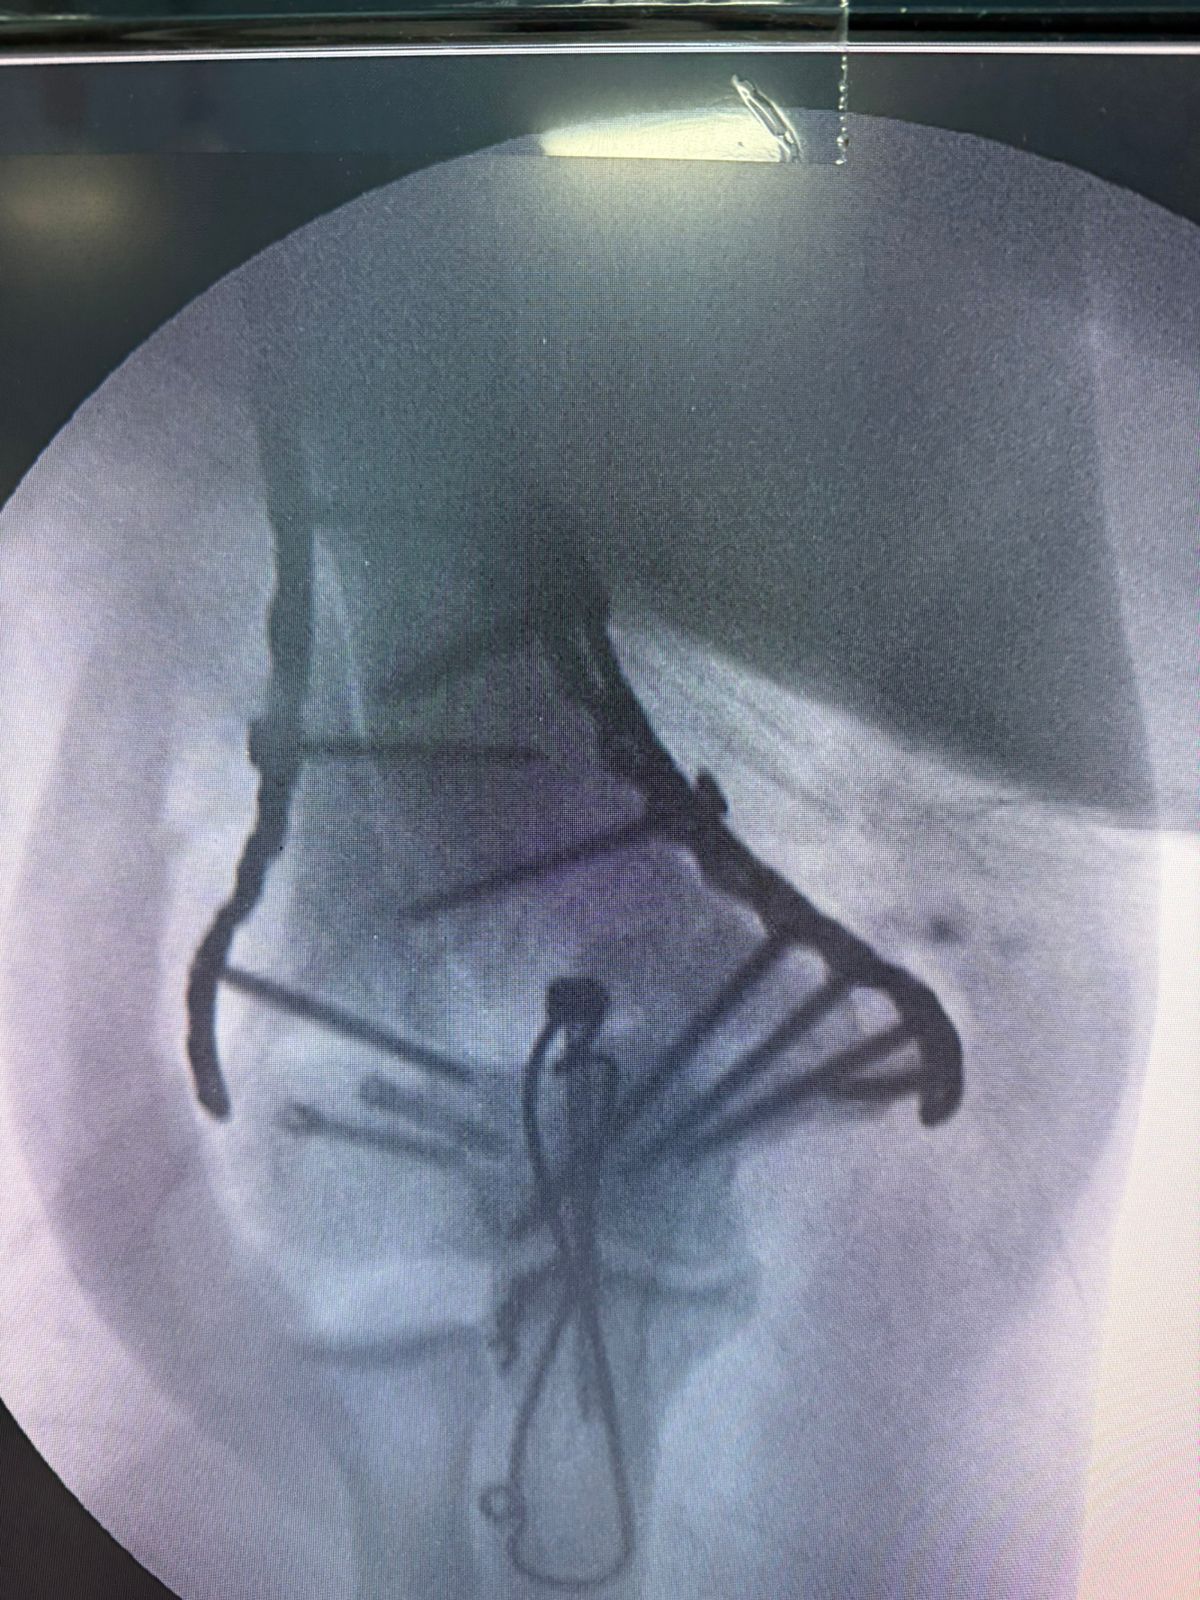

Moments That Mark Meaningful Recovery

Witness real patient transformations at The Ortho Clinic through images that reflect successful treatments and restored mobility.